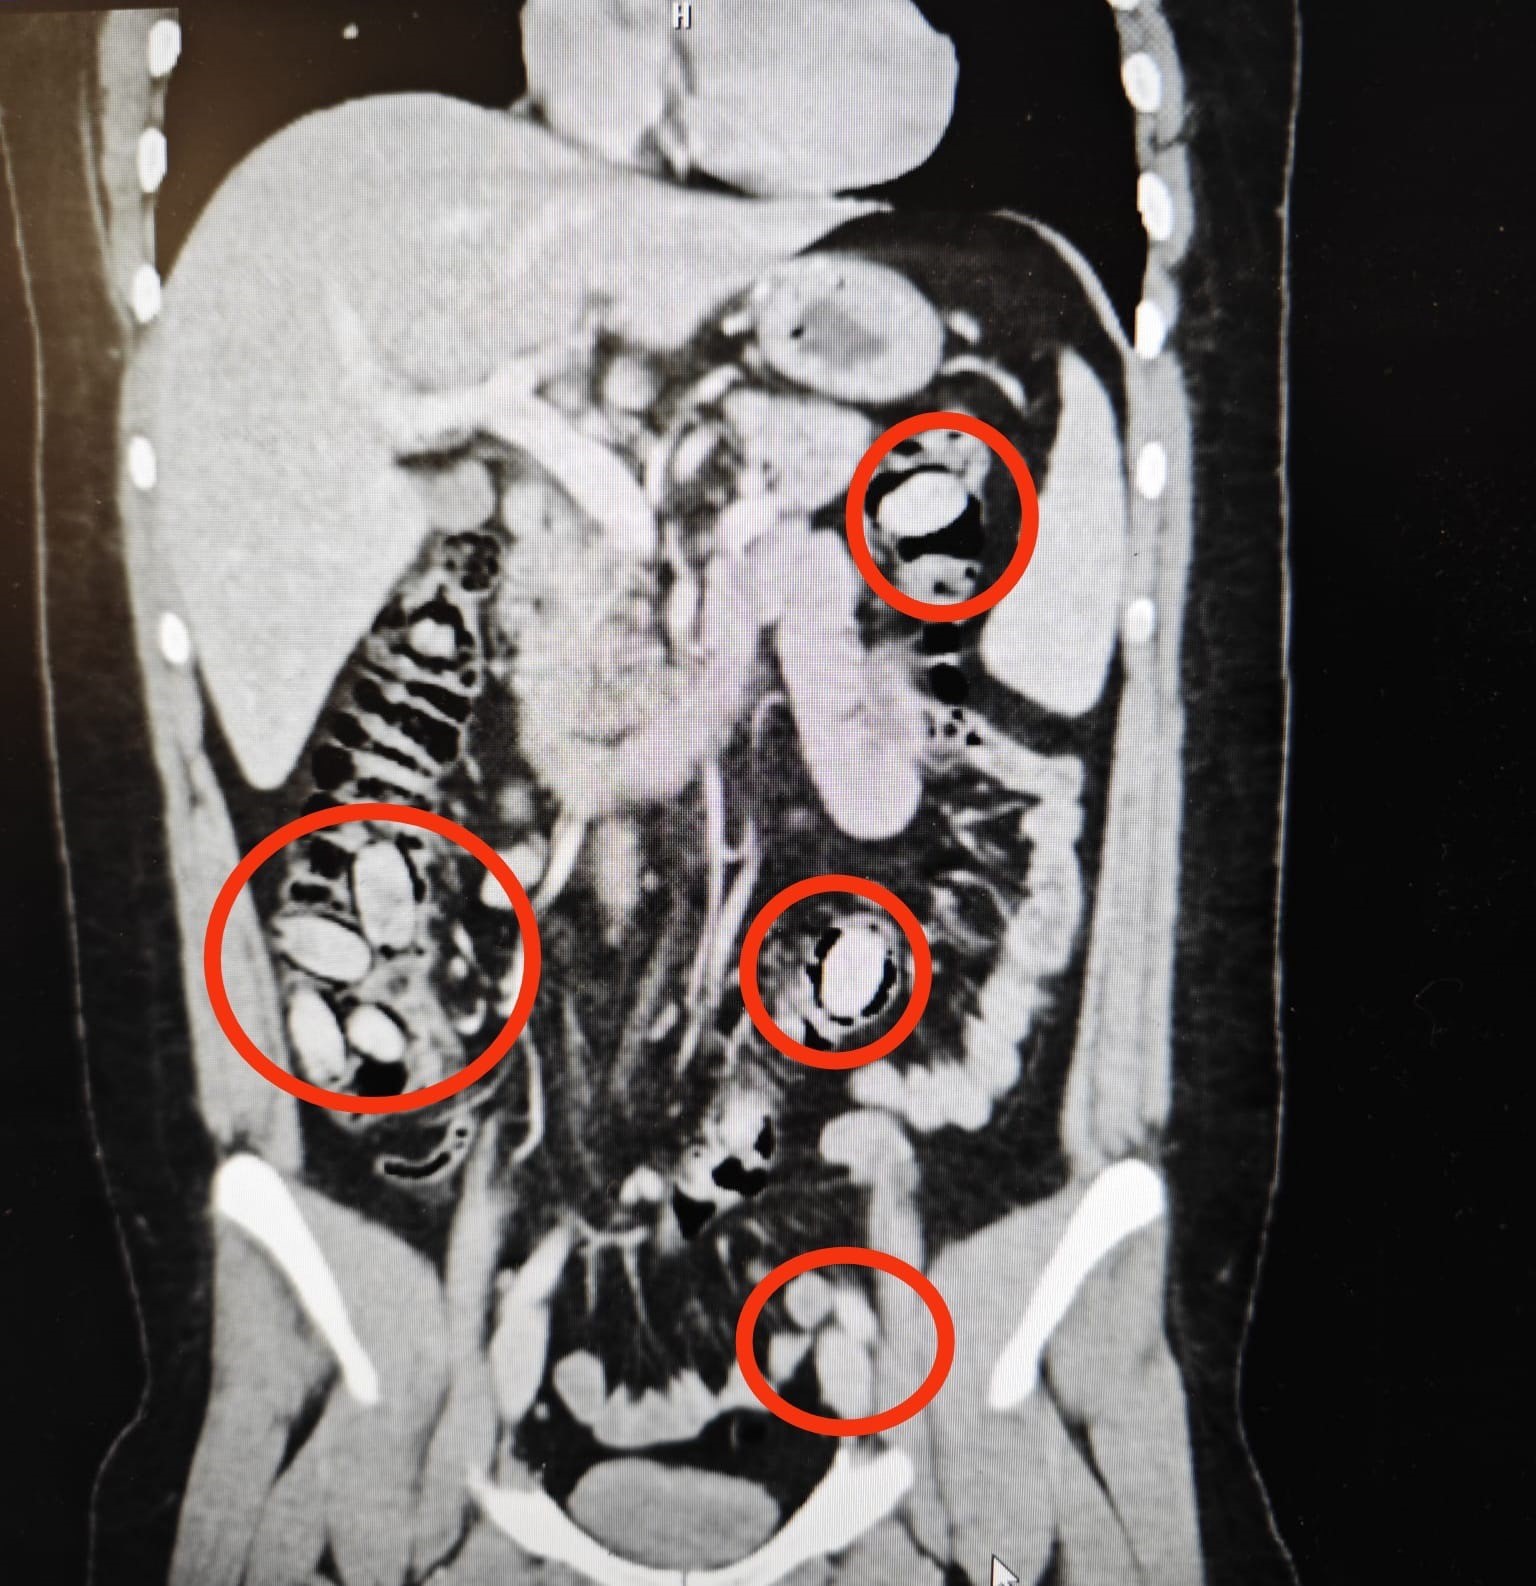

Hastanede yapılan tetkikler sonucunda, S.A.’nın yutmak suretiyle midesinde 44 kapsül metamfetamin taşıdığı belirlendi. Uyuşturucu maddelerin insan sağlığı açısından risk oluşturması nedeniyle cerrahi müdahale kararı alındı.

Ameliyatla Çıkarıldı

Gerçekleştirilen cerrahi operasyonla, midedeki kapsüller tek tek çıkarıldı. Şahsın sağlık durumunun kontrol altına alınmasının ardından adli işlemler başlatıldı.